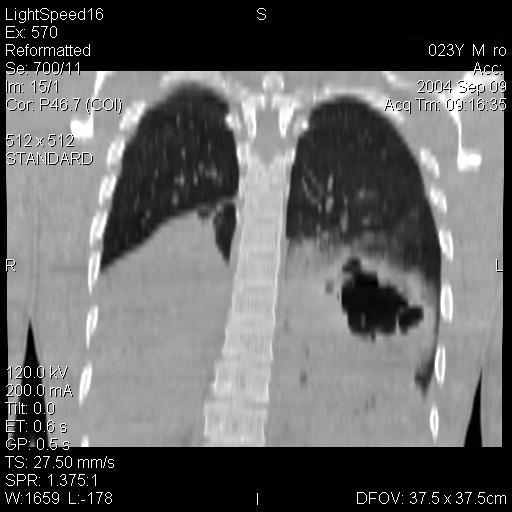

08.10.2004г. произведена люмбальная пункция. Ликвор розового цвета, слегка мутный. Микроскопия: эритроциты в большом количестве – 10200 в мм3, белок – 0,297‰, лейкоциты – 5 в мм3, реакция Панди положительная. На рентгенограммах позвоночника определяется снижение высоты тел ThXI, ThXII на 0,5 см. На рентгенограммах и компьютерных томограммах органов грудной клетки слева в X сегменте определяется полостное образование размерами 5×5 см с четким неровным внутренним контуром и размытым наружным, за счет перифокальной инфильтрации лёгочной ткани (рис.1). При компьютерной томографии головного мозга выявлен перелом основания черепа в области передней и средней черепных ямок. Ушиб головного мозга. Очаг контузии в левой лобной доле, эпидуральный сгусток объёмом 3-4 мл в правой лобной доле. При ультразвуковом исследовании органов брюшной полости под правой долей печени определяется небольшое количество свободной жидкости. Больному проведена лапароскопия – в брюшной полости обнаружено 200 мл жидкой крови, гематома в области брыжейки нисходящей ободочной кишки.

Рис.1. Рентгенограммы и компьютерные томограммы больного Ш., 31 г. при поступлении в клинику.